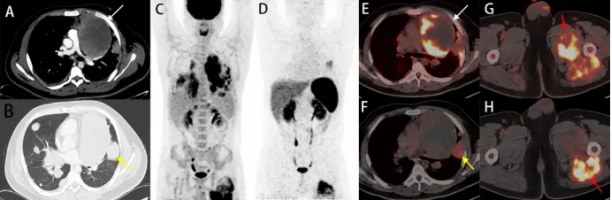

王瑞民/孟晓琳:罕见病原发性肺上皮样...